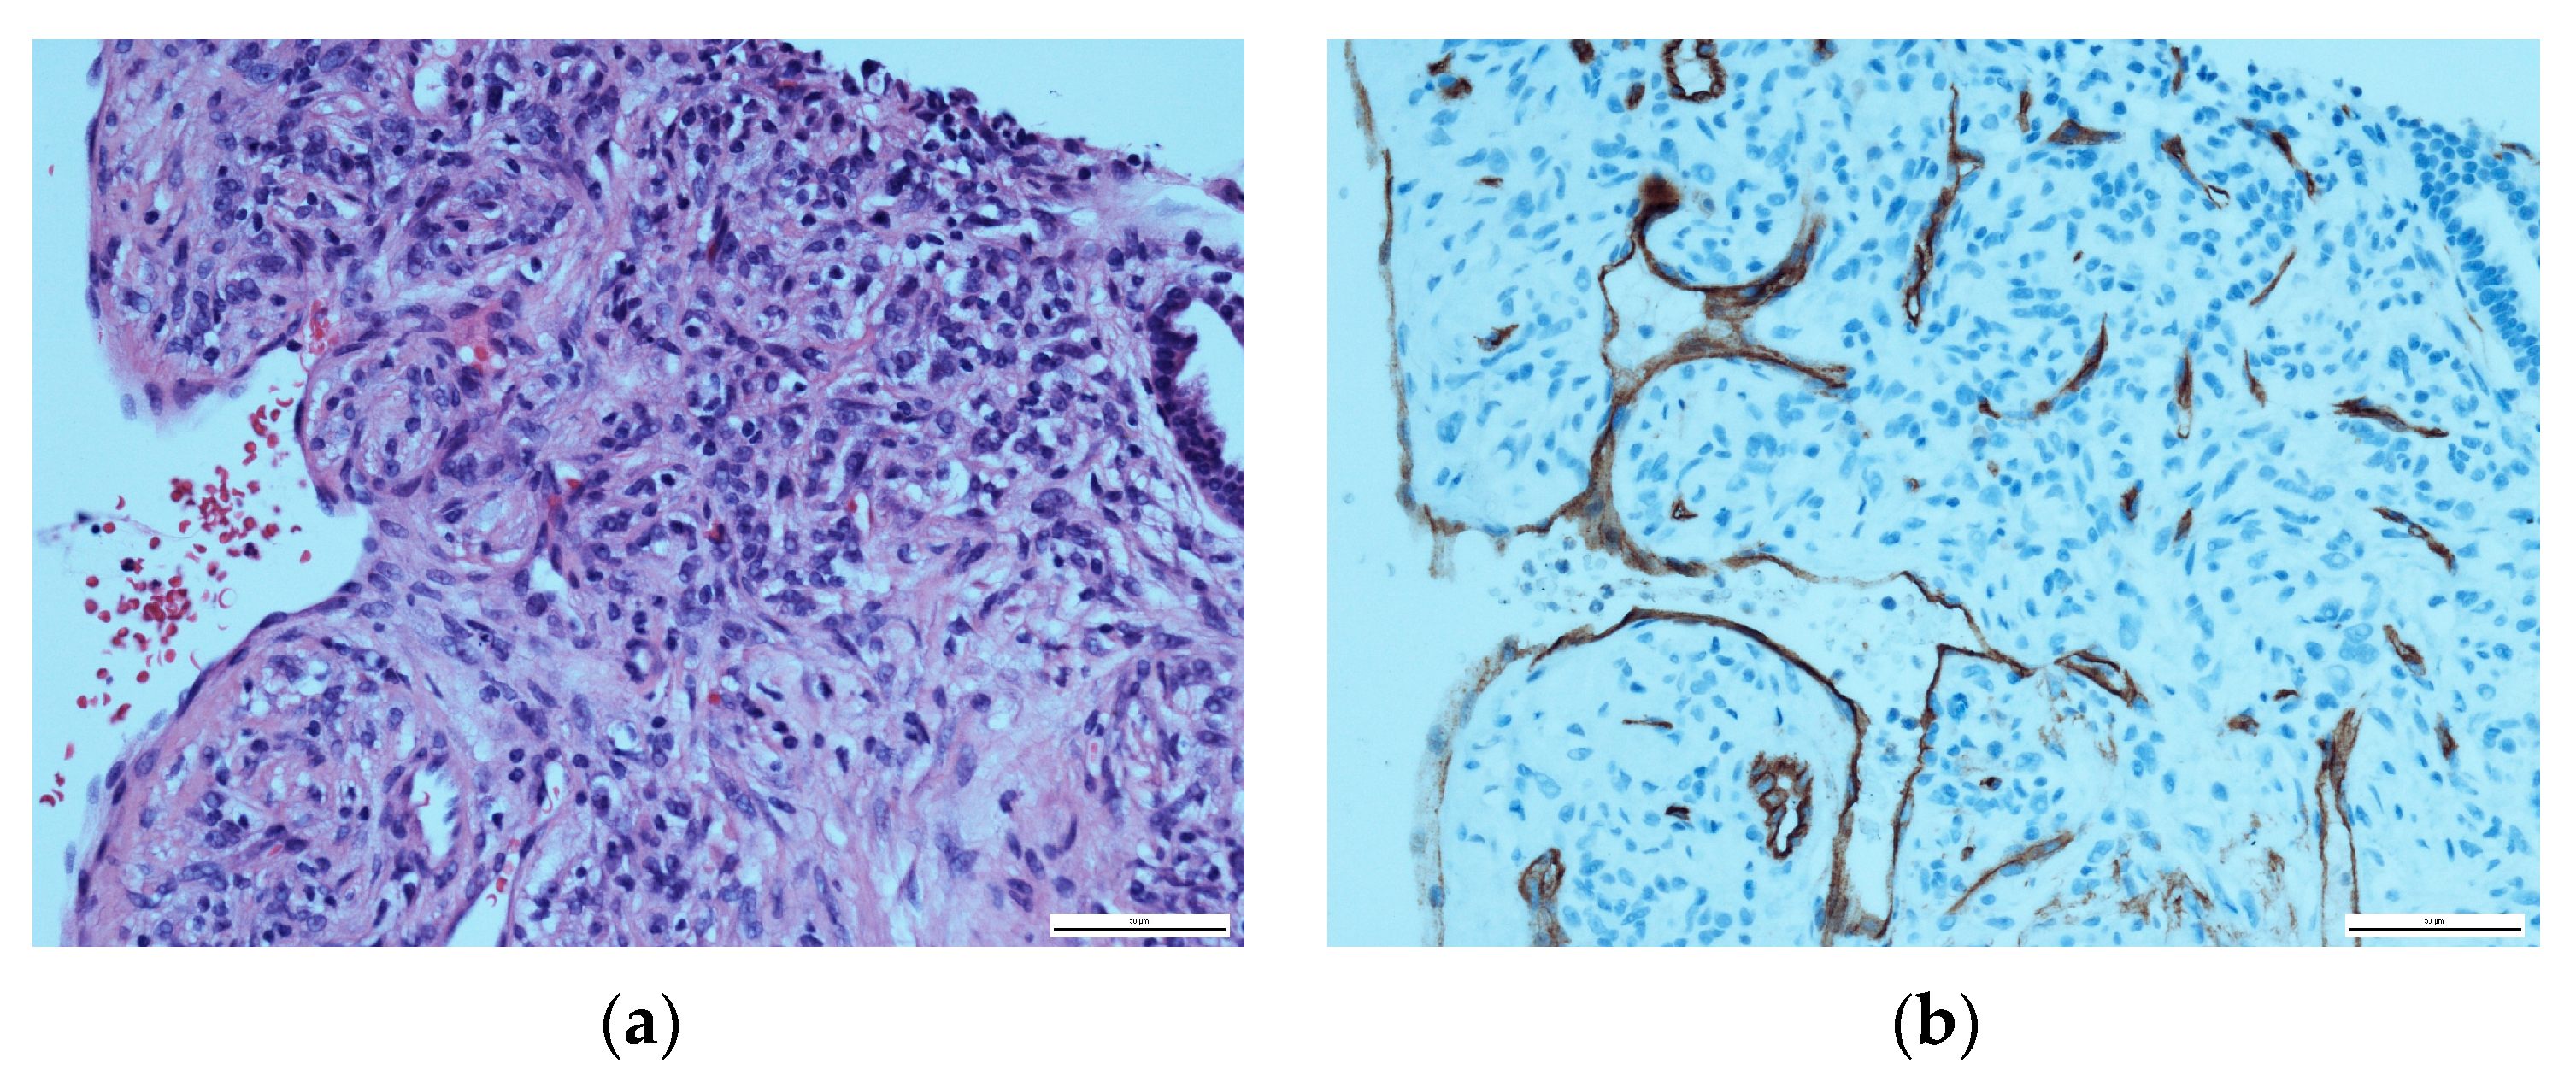

Upon histopathological evaluation, a solid mass composed of spindle cells mixed with few round cells was reported (Figure 4a). In immunohistochemical staining, the spindle cells partially tested positive for the expression of CD34 and weakly positive for smooth muscle actin (Figure 4b). Significant histopathological similarities between the nuchal tumour and the pulmonary mass were confirmed to the point of a unilateral agreement on the presence of pulmonary metastasis. Due to the nuchal tumour’s recent aggressive growth, a multidisciplinary board conference extensively discussed treatment options. Surgical excision of the nuchal tumour was recommended. However, the patient chose a watch-and-wait approach due to reporting a subjective lack of symptoms at this point in time. In an initial follow-up by the surgical department a month after the multidisciplinary board conference, the nuchal tumour was stable and constant in size.

Figure 4. Histopathological evaluation of the solid pulmonary mass: (a) HE staining, showing a majority of spindle cells with a few round cells at ×400; (b) CD34-positive immunohistochemical staining of the spindle cells.